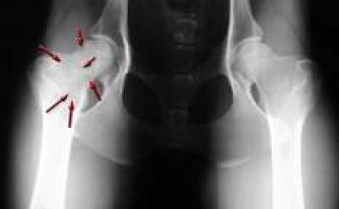

Ung thư xương là ung thư liên kết xuất phát từ tế bào tạo xương, tạo sụn, tế bào mô liên kết của xương. Ung thư xương khá hiếm gặp, chiếm khoảng 0,5% trong số trường hợp ung thư. Những vị trí ung thư xương thường gặp là ở đầu trên xương chày, đầu dưới xương đùi, đầu trên xương cánh tay, đầu dưới xương quay.

Những biểu hiện thường gặp của ung thư xương như là đau mơ hồ trong xương, sau đó những cơn đau bắt đầu rỡ hơn và vô cùng khó chịu. Triệu chứng khối u có thể xuất hiện trước, đồng thời hoặc sau biểu hiện đau. U khởi đầu là một đám sưng, chắc, nổi gồ mặt da, bờ không rõ, nắn không đau. Về sau, u to nhanh, gây biến dạng. U xâm lấn phần mềm, đau khi khám. U gây tân tạo mạch, da ấm nóng hơn nơi khác. Mật độ u nơi mềm, nơi chắc, nơi căng do tụ máu.

Ngoài việc dựa vào những biểu hiện lâm sàng, các bác sỹ có thể tiến hành chụp phim Xquang, chụp MRI và CT và sinh thiết… để chẩn đoán có khối u hay không và có là u ác tính hay lành tính. Khi gặp những dấu hiệu ở trên tốt nhất nên đi khám để điều trị kịp thời.